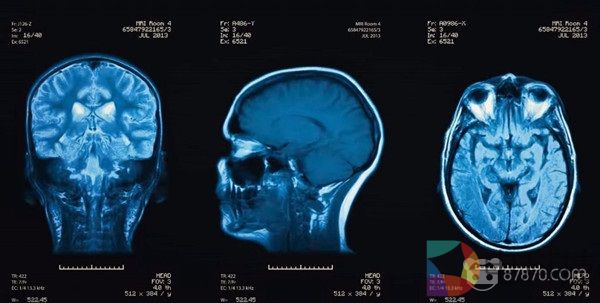

CrashCourse正式公布脑部保护VR课程内容

根据《美国医学会杂志》2017年的一份报告,五分之一的高中运动员(20%)会有不同程度上的脑震荡。这是一个惊人的统计数字。脑震荡通常被称为“隐形损伤”,是最常见的运动损伤之一。这个问题的很大一部分不仅仅是缺乏意识,而是缺乏关于如何发现脑震荡以及如何治疗脑震荡的教育。这就是CrashCourse的作用。(原文)